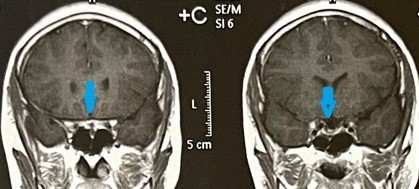

Magnetic resonance image of a patient suffering from a tumor of the skull base compressing the right optic nerve and the right carotid artery. Before and after successful microsurgical excision of the tumor.